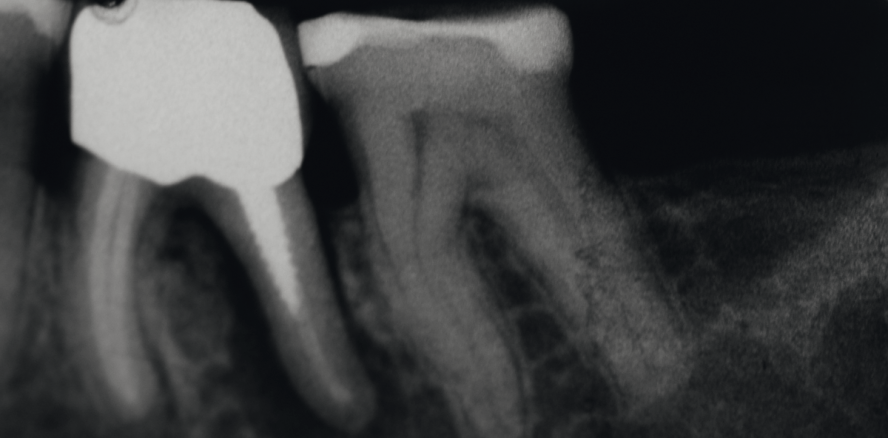

Bevor eine Wurzelkanalbehandlung durchgeführt wird, muss entschieden werden, ob der Zahn mit sinnvollem Aufwand restauriert und erhalten werden kann oder ob der Defekt bereits so fortgeschritten ist, dass ein Zahnerhalt langfristig nicht möglich ist (Abb. 1). Eine Entscheidung, ob die Wurzelkanalbehandlung in der Privatpraxis erfolgen kann oder ob ein Spezialist beigezogen werden muss, sollte relativ früh erfolgen. Bei mehrwurzeligen Zähnen muss geprüft werden, ob ein Teilerhalt des Zahnes mittels Wurzelamputation oder Hemisektion sinnvoll ist. Der Patient sollte in die Therapieentscheidung einbezogen und über die Kosten und die vermutete Prognose informiert werden. Grundsätzlich hat die Wurzelkanalbehandlung, sofern diese nach den gängigen Qualitätsleitlinien durchgeführt wird, eine gute Prognose (85 bis 95 Prozent Erfolg).

Dank der Adhäsivtechnik muss nicht jeder Höcker im Seitenzahnbereich bei einem wurzelkanalbehandelten Zahn eingekürzt werden. Es ist aber wichtig, dass genügend Restzahnhartsubstanz vorhanden ist, denn spätere Zahnfrakturen sind oftmals fatal, da sie dünn auslaufend in den Alveolarkamm ziehen (Abb. 2). Nicht selten kann eine derartige Fraktur zum Verlust des Zahnes führen. Darum gilt: Im Zweifelsfall schwache Zahnwände im Seitenzahnbereich kürzen und okklusal mit der Restauration überdecken.